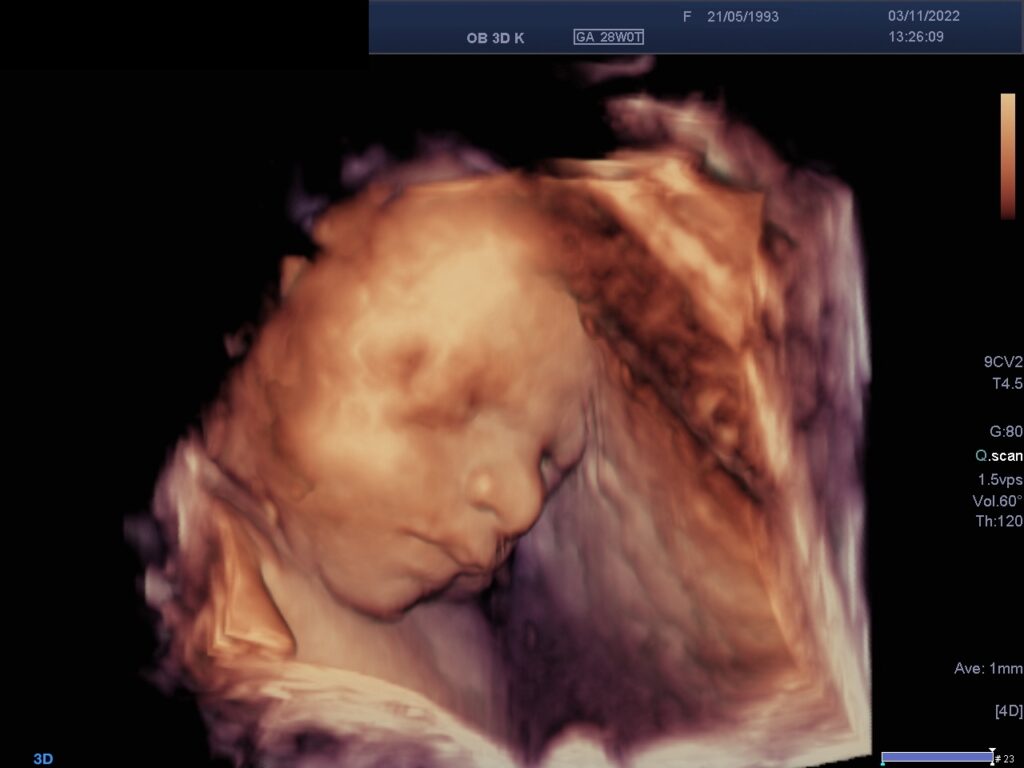

3D-/ 4D- Sonographie

Bei der 3D-Sonographie werden die normalen 2D- Schnittebenen des Ultraschalls in einem Volumenblock zusammengefasst, ähnlich der Computertomographie. Ermöglicht wird dies i.d.R. durch spezielle Schallköpfe, die in der Lage sind, Ultraschallebenen mit definierten Abständen direkt hintereinander abzutasten. Danach ist es möglich, neue Schnittebenen aus diesem Volumenblock zu rekonstruieren, die aber nicht an die Qualität der Originalebenen heranreichen. Neben anderer Darstellungsmöglichkeiten ist besonders das Oberflächenrendering bekannt, in dem vor allem das fetale Profil eindrucksvoll dargestellt werden kann.

So kann die 3D-Sonographie in manchen Fällen zu einer Ergänzung der Diagnostik führen.

Die 3D-Sonographie ermöglicht die plastische Darstellung des Feten.